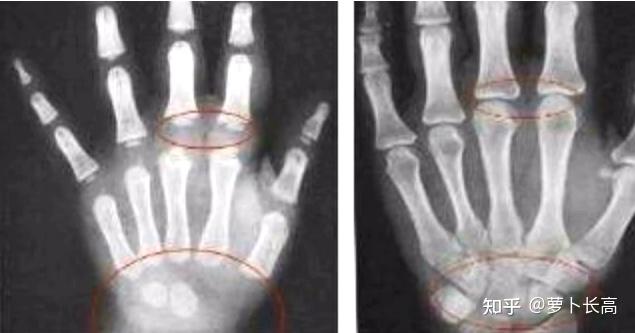

这张骨的图片,左边是还没有闭合,就是存在一条小缝,然后右边的话是

图片尺寸635x333